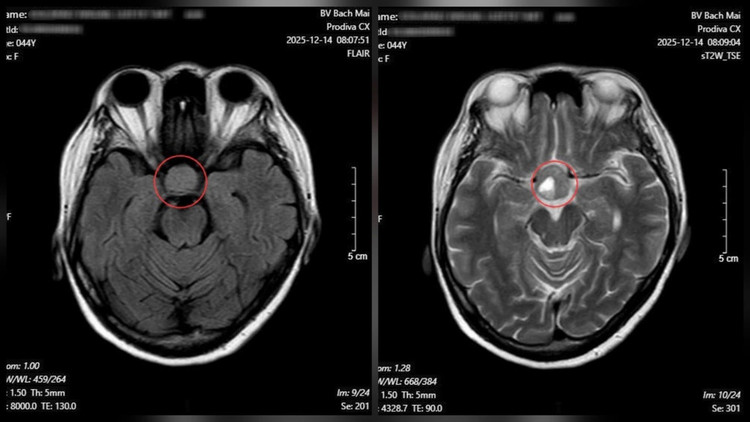

Từ những dấu hiệu trên, bệnh nhân được chỉ định chụp cộng hưởng từ (MRI) sọ não. Kết quả cho thấy một khối u tuyến yên kích thước lớn (macroadenoma), kích thước 26 × 21 mm.

Kết quả chụp cộng hưởng từ (MRI) sọ não cho thấy một khối u tuyến yên kích thước lớn - Ảnh BVCC